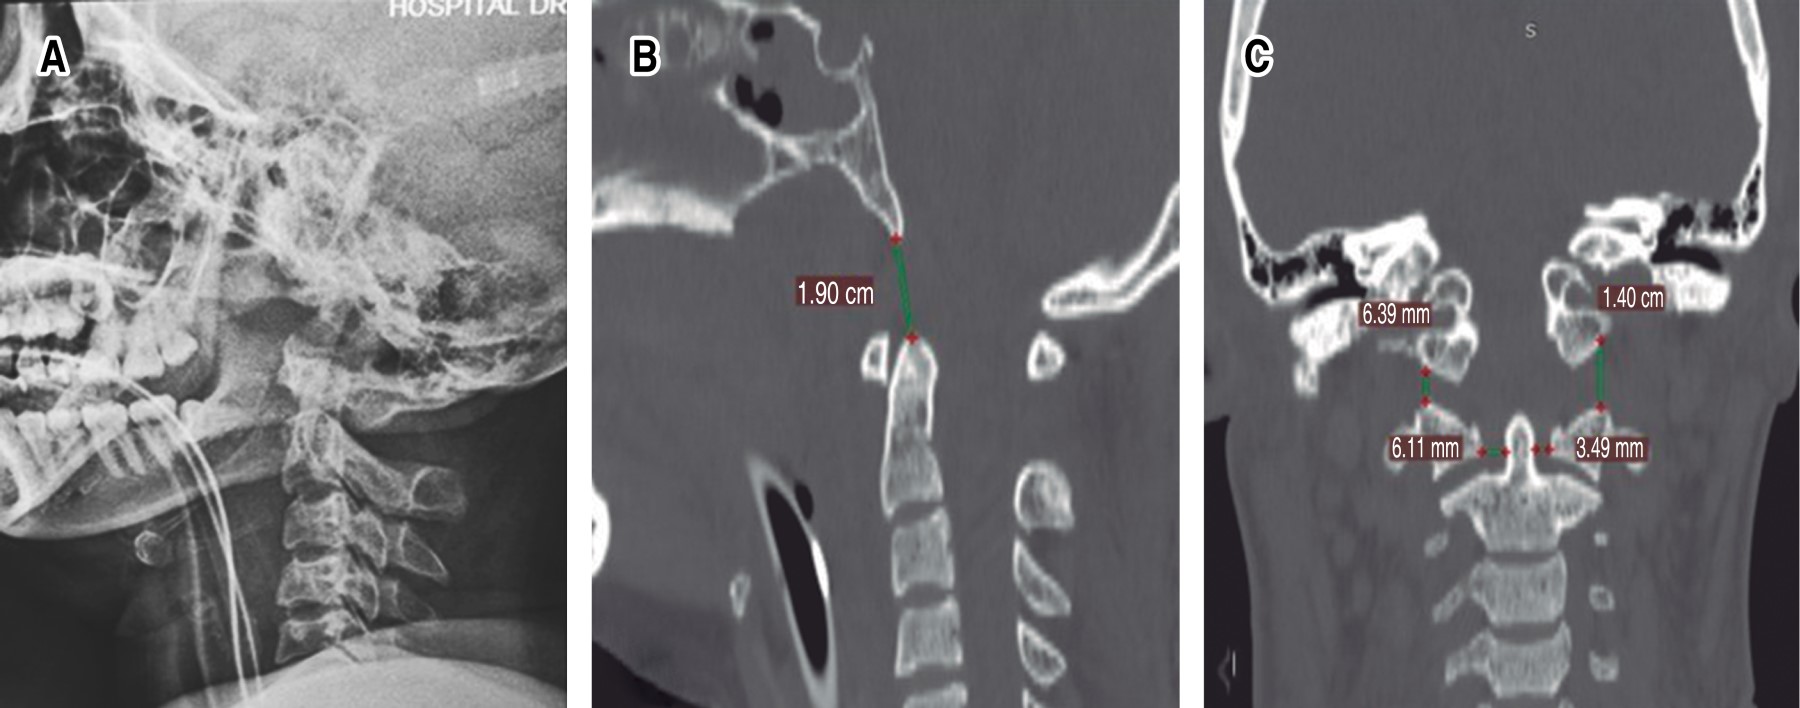

Introduction: injuries to the craniocervical junction with instability secondary to trauma are rare; with complications with a high mortality rate. When both lesions are present; the patient's prognosis for survival and recovery is usually very poor. Surgical treatment for reconstruction of the occipitocervical junction are complex and uncommon procedures; in most cases they have been studied in the treatment of degenerative and rheumatic pathologies. Clinical case: 27-year-old female patient, with combined occipitoatloid-atlantoaxial instability secondary to an accident in a motorcycle-type vehicle; which has multiple injuries. Diagnosis: clinic with neurological deficit; radiological studies of trauma, and axial tomography of the skull and spine, where data of instability at the C0-C1 and C1-C2 levels are evident. Interventions: multidisciplinary management and subsequently occipitocervical reduction and fixation with Harms technique of the injuries due to traumatic vertebral instability; C0-C1, C1-C2 and C2-C3. Follow-up: 9 months after the intervention, with adequate clinical evolution. Conclusions: although there are few publications and guides on the diagnosis, ideal moment of intervention and optimal stabilization method in cases of instability due to trauma, we recommend a multidisciplinary approach. Early diagnosis and treatment directly influence the final prognosis and quality of life of these patients.

Figure 3